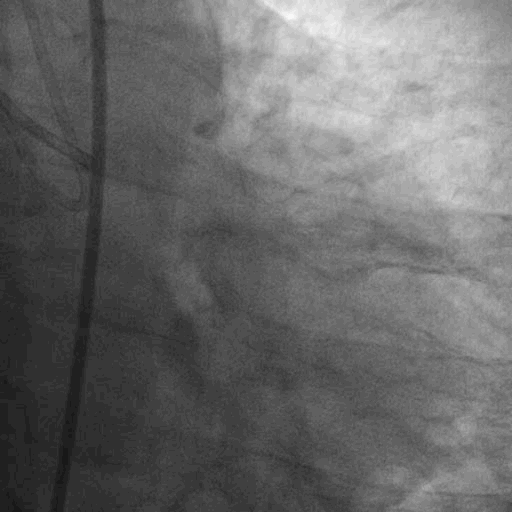

术前造影:

双侧造影: